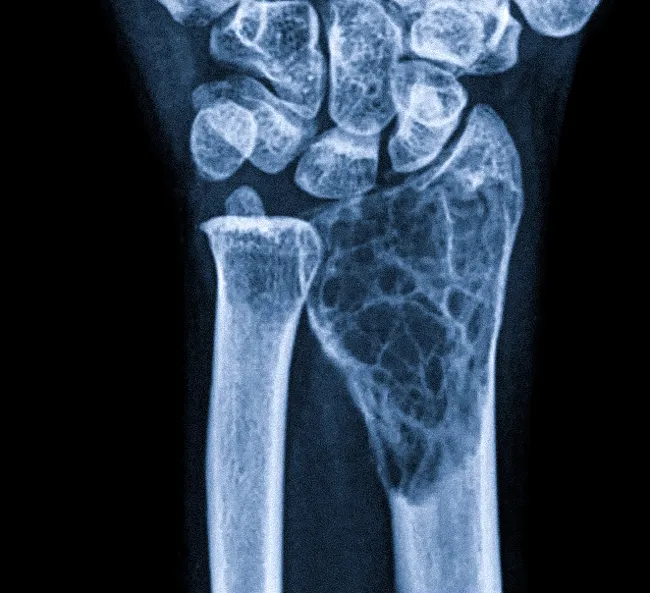

- Рентгенография. Это ключевой метод диагностики. Рентгеновский снимок кисти в прямой проекции позволяет детально рассмотреть кости пальцев, подтвердить наличие аномальной трапециевидной или треугольной средней фаланги и точно измерить угол деформации.